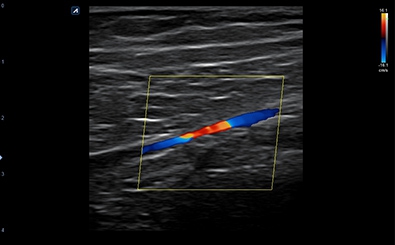

CLINICAL IMAGES

臨床影像

Peripheral Artery